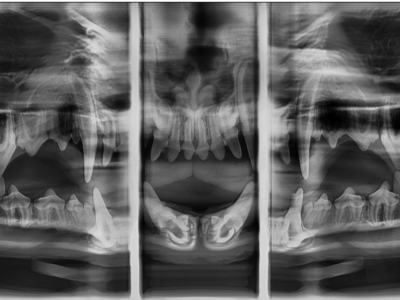

Dental surgeries are recommended based on your dog or cat’s oral hygiene and overall dental health. Our clinic provides comprehensive dental procedures, which include full-mouth digital dental x-rays (the world’s first veterinary specialized panoramic dental x-ray system, actual scan times 15 seconds for full mouth. Panoramic images provide more coverage for bone defect and jaw lesions), thorough dental cleaning, and any required or suggested extractions.